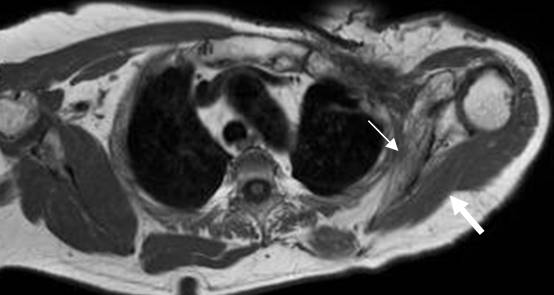

Fig 143. Neuropraxia.

A: RM coronal en T1y B: RM coronal en STIR. Cambios inflamatorios por encima de los vasos subclavios, que rodean las raíces nerviosas, las cuales permanecen integras. La lesión se produjo después de una luxación de hombro.